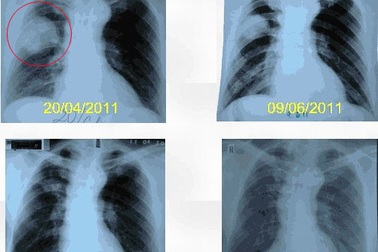

Đốt u phổi bằng sóng cao tần, hi vọng mới của bệnh nhân ung thưĐốt khối u phổi ác tính bằng sóng cao tần là kỹ thuật mới trong điều trị ung thư phổi đang được thực hiện khá thành công tại bệnh viện Phạm Ngọc Thạch trong 2 năm qua với 40 bệnh nhân.